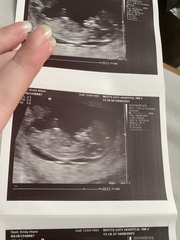

Nub theory boy or girl 💙💕

What do we think?

Girl

Girl. It’s horizontal.

Baby is a confirmed baby boy 👦 x